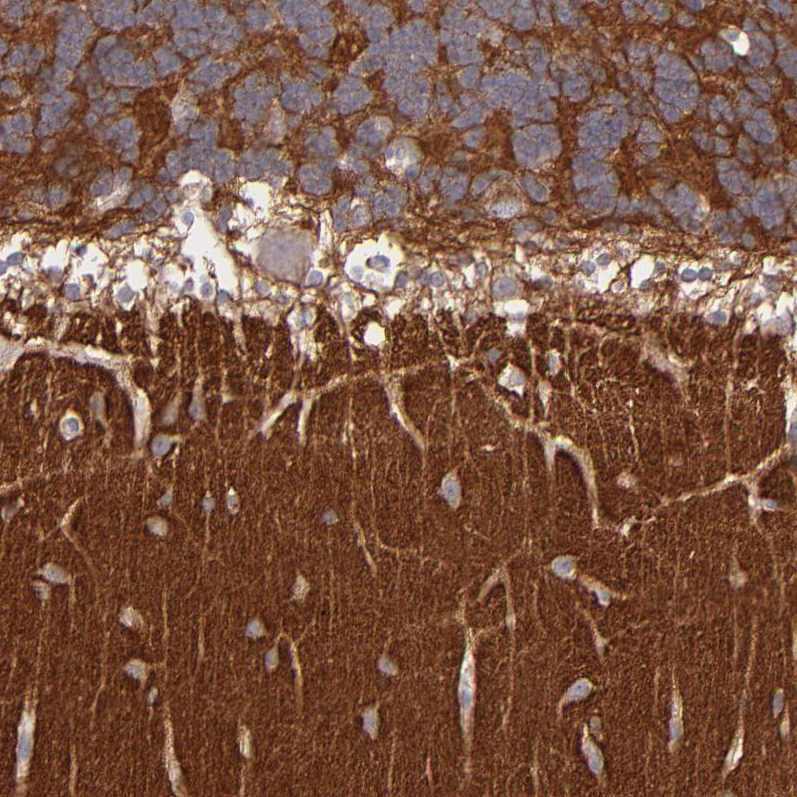

Immunohistochemistry analysis in human cerebral cortex and liver tissues using HPA003011 antibody. Corresponding GNAZ RNA-seq data are presented for the same tissues.